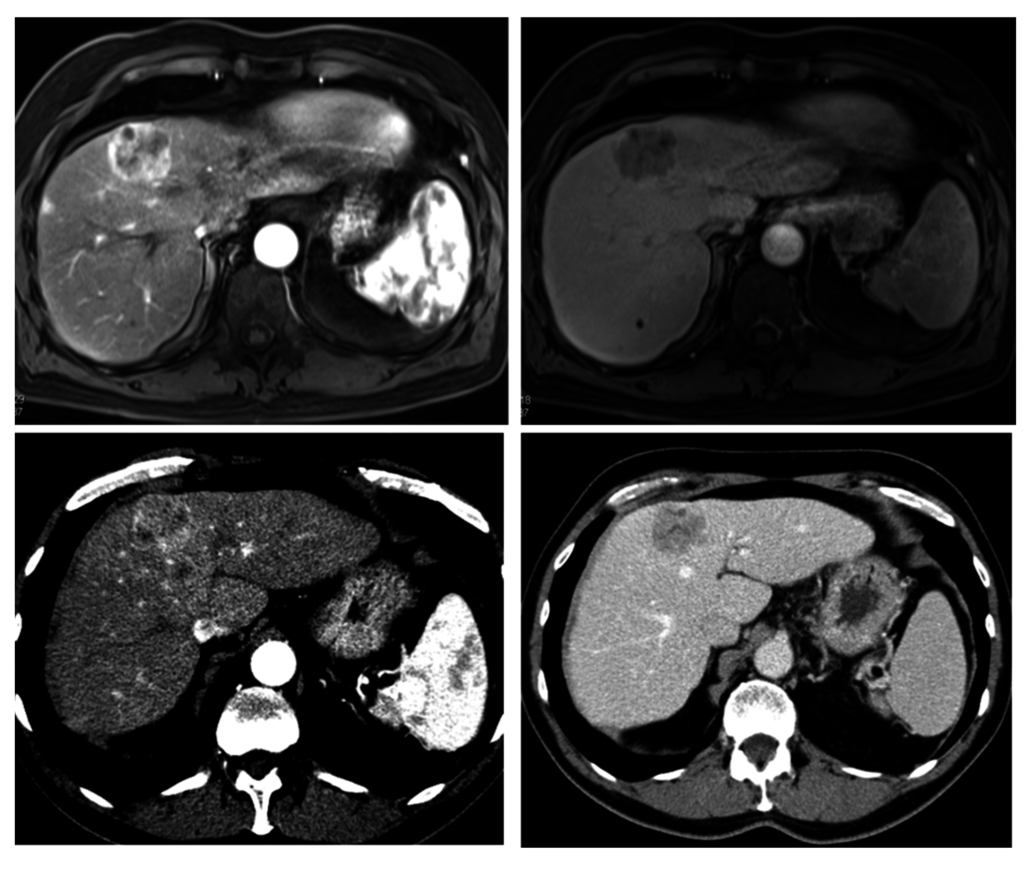

4. Computed Tomography (CT)

4.1. Advances in CT Imaging

4.2. Dual-Energy CT (DECT)

- Anzidei, M.; Di Martino, M.; Sacconi, B.; Saba, L.; Boni, F.; Zaccagna, F.; Geiger, D.; Kirchin, M.A.; Napoli, A.; Bezzi, M.; et al. Evaluation of image quality, radiation dose and diagnostic performance of dual-energy CT datasets in patients with hepatocellular carcinoma. Clin. Radiol. 2015, 70, 996–973. [Google Scholar] [CrossRef] [PubMed]

- Dai, X.; Schlemmer, H.P.; Schmidt, B.; Hoh, K.; Xu, K.; Ganten, T.M.; Ganten, M.K. Quantitative therapy response assessment by volumetric iodine-uptake measurement: Initial experience in patients with advanced hepatocellular carcinoma treated with sorafenib. Eur. J. Radiol. 2013, 82, 327–334. [Google Scholar] [CrossRef] [PubMed]

- Okada, M.; Kim, T.; Murakami, T. Hepatocellular nodules in liver cirrhosis: State of the art CT evaluation (perfusion CT/volume helical shuttle scan/dual-energy CT, etc.). Abdom. Imaging 2011, 36, 273–281. [Google Scholar] [CrossRef] [PubMed]